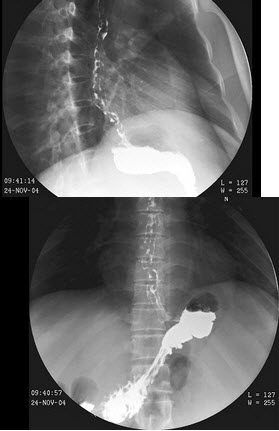

104、单项选择题

男,70岁,进行性吞咽困难半年,结合图像,最可能的诊断为()

A.正常食管

B.食管静脉曲张

C.食管平滑肌瘤

D.贲门失弛缓

E.食管癌